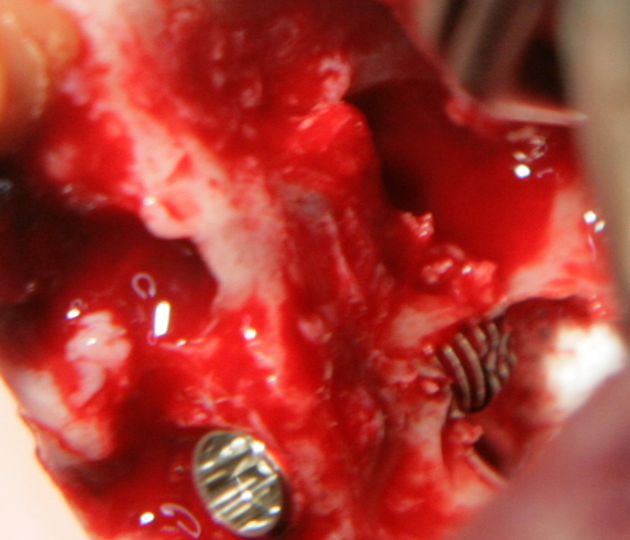

Отворен максиларен синус в началото на интервенцията. Случаят е интересен със следното - твърде атипична форма на трепанационния отвор. На какво се дължи на това - на лошо планиране на оперативния достъп или на нещо друго? Дължи се на факта, че отначало въпросната намеса беше планирана като балонен синуслифт; за съжаление обаче мембраната на синуса се разкъса и надуването на балона стана невъзможно.